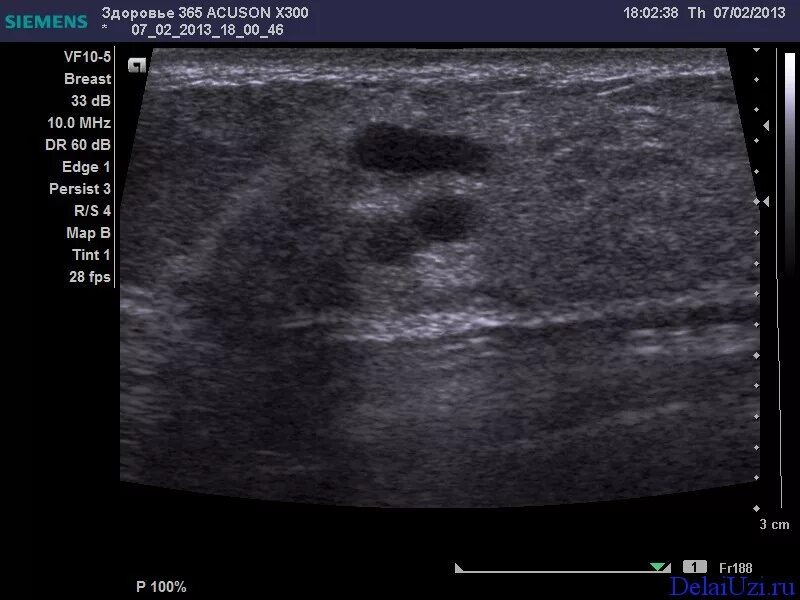

Где можно сделать узи молочной железы